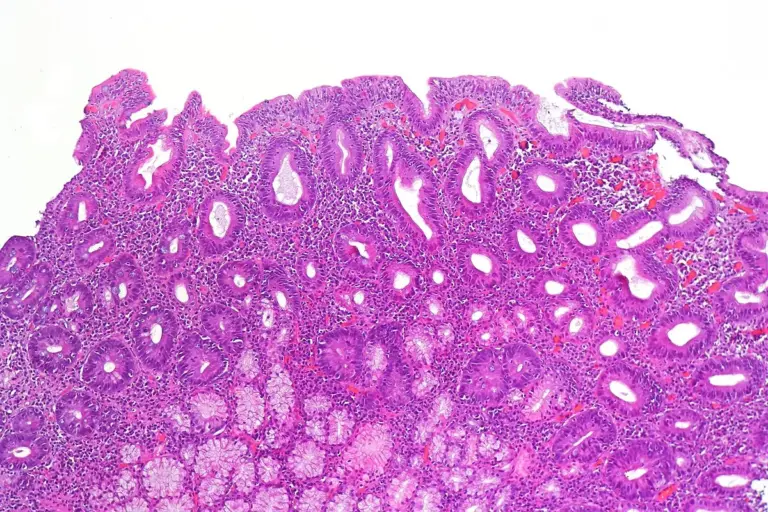

The selection of celiac disease treatments is unique in the medical world because the primary “medicine” is a total and permanent lifestyle change. There are no pills or surgeries that can cure the condition, but strict dietary management is highly effective. The goals of clinical management are to stop the autoimmune attack, allow the intestinal villi to regrow, and correct any nutritional gaps. At Liv Hospital, we provide a multidisciplinary support system to help you navigate this transition, ensuring that your diet is safe, varied, and nutritionally complete.

The cornerstone of recovery is the total elimination of gluten from the environment. This requires a much deeper level of commitment than a standard diet.

In a small percentage of clinical cases, the intestine does not heal despite a strict gluten free diet. This is known as refractory disease.

Restoring the balance of the gut flora is a key therapeutic goal after years of inflammation.